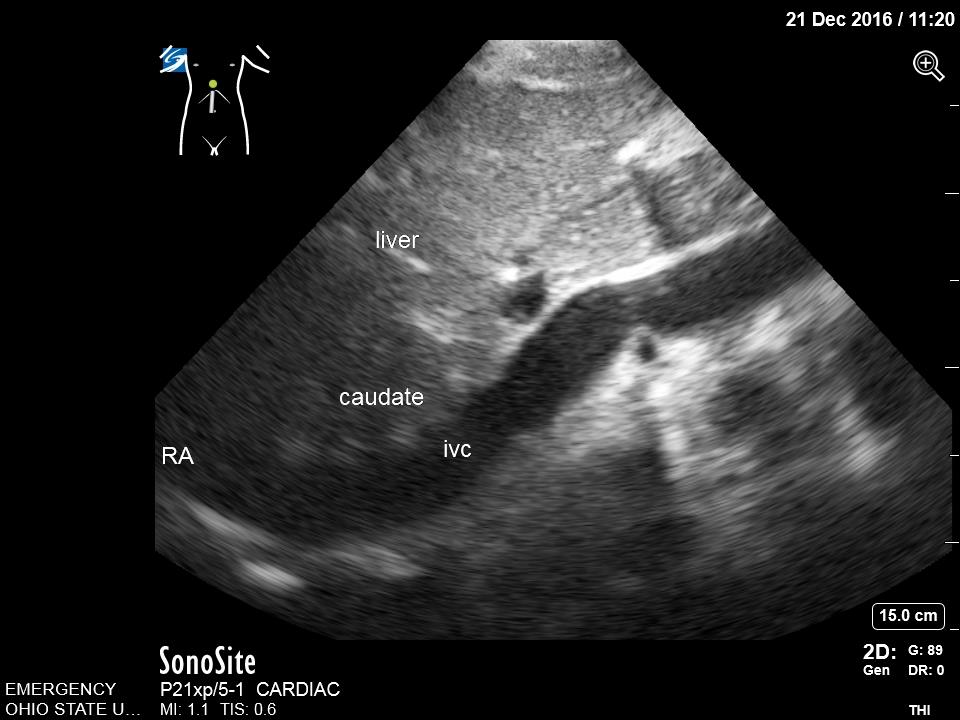

- Fan inferiorly to visualize the IVC in short axis. Rotate the transducer 180 degrees clockwise to visualize IVC in long axis. Note overall diameter and collapsibility with respirations approximately 2-3 cm distal from the right atria or just distal to the insertion of the hepatic vein.

- Figure 7. Subcostal Inferior Vena Cava in Long Axis. IVC = inferior vena cava. Caudate = caudate lobe of the liver. RA = right atrium